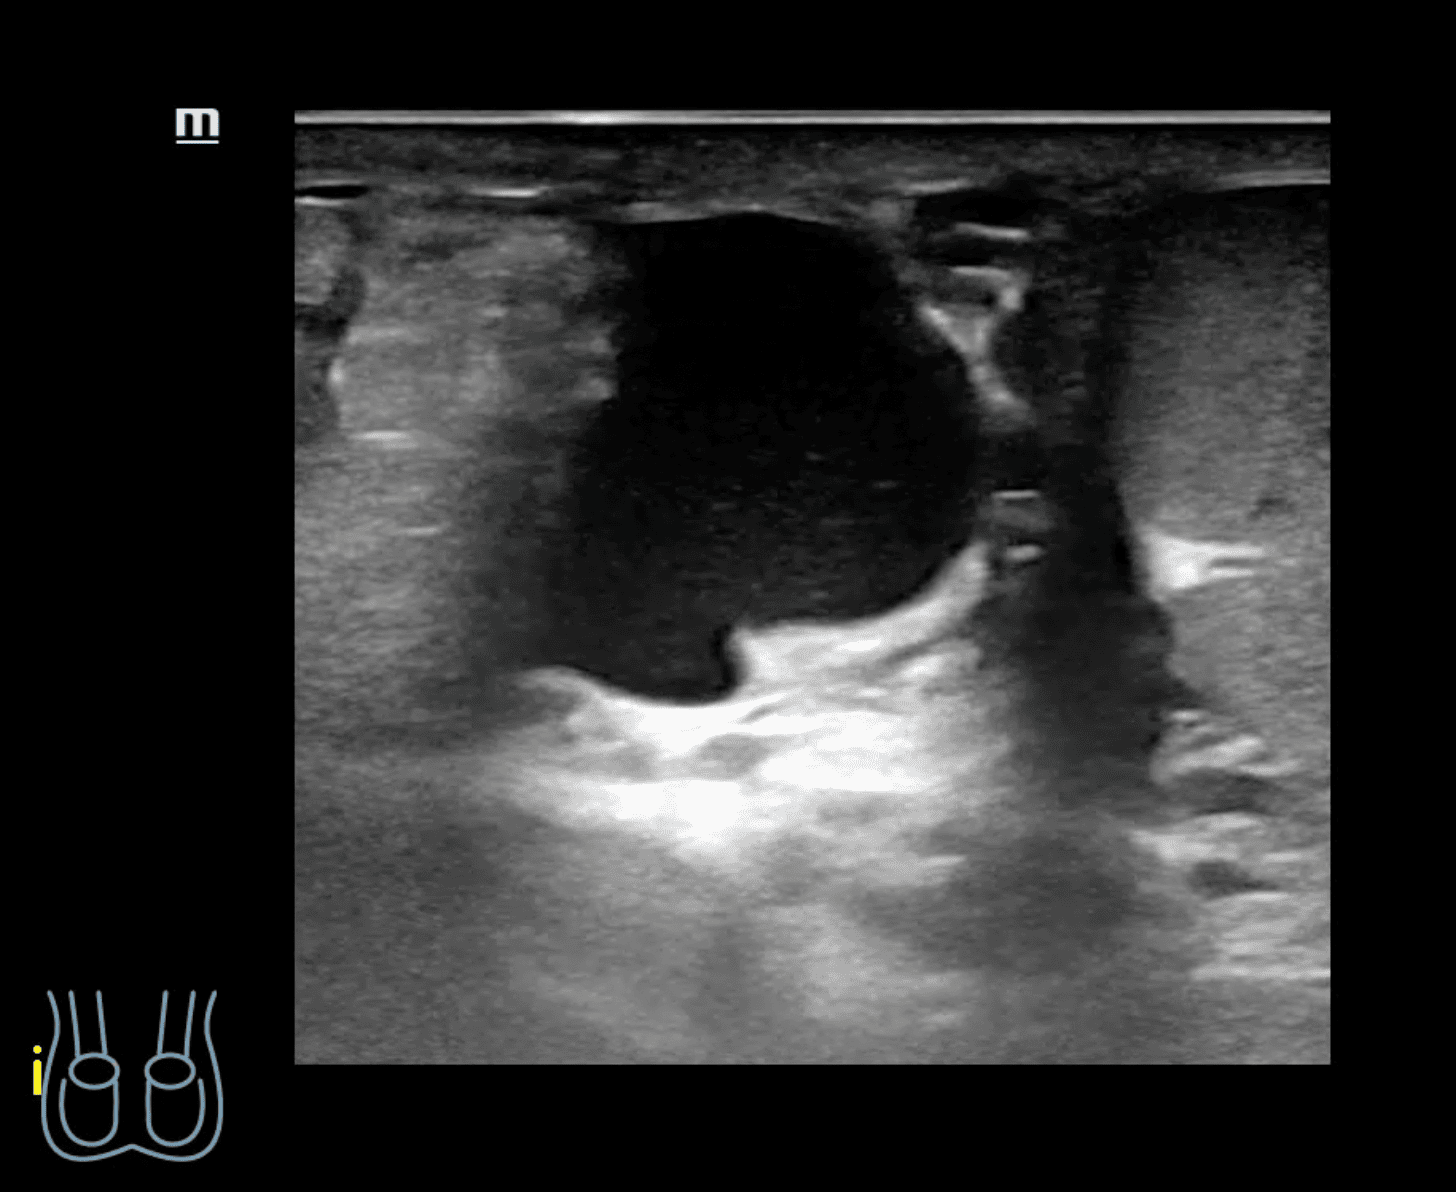

A nivel de escroto derecho, se observa imagen heterogénea con contenido intestinal compatible con hernia inguino-escrotal derecha. Testículos de aspecto normal.

Hernia inguino-escrotal derecha reductible dolorosa, no complicada.